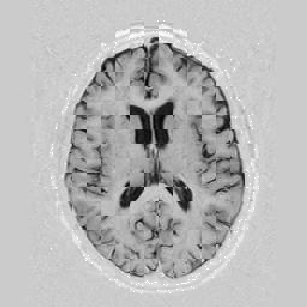

The results are shown for another pair of images in Figure [*].

Figure: Multi-scale NRR. From left to right, top then bottom: before NRR; after 5 iterations of NRR at level 2; after another 5 iterations of NRR at level 1.